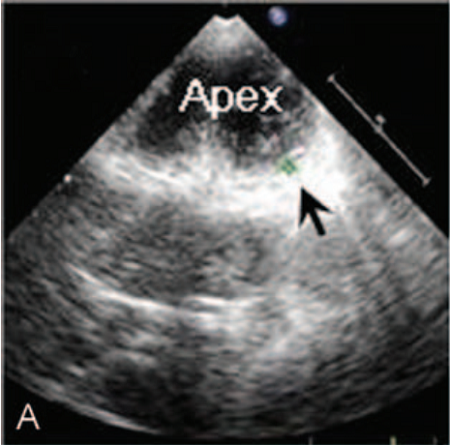

青年男性,34岁,反复胸部针刺样疼痛及头晕1年。除低血压和"神经衰弱"之外,既往无特殊病史,不抽烟、酗酒,无心脏病家族史。患者年轻的时候身体虚弱。入院时血压110/70 mmHg,心率72次/分,体检无特殊。心电图和胸部X光显示正常。但超声心动图却有重大发现,提示左心室壁乳头肌水平以下小梁增加,心内膜壁深层交界凹陷,特别是在心尖部游离壁(图A),其小梁厚度为9mm,心肌变得更薄;心尖搏动减弱,二尖瓣见血液反流(图B),LVEF 57%。冠脉CTA显示左前降支(LAD)心肌桥,长度为38.9 cm(图C、D),余冠脉未见明显异常。

图A 心内膜壁深层交界凹陷,特别是在心尖部游离壁